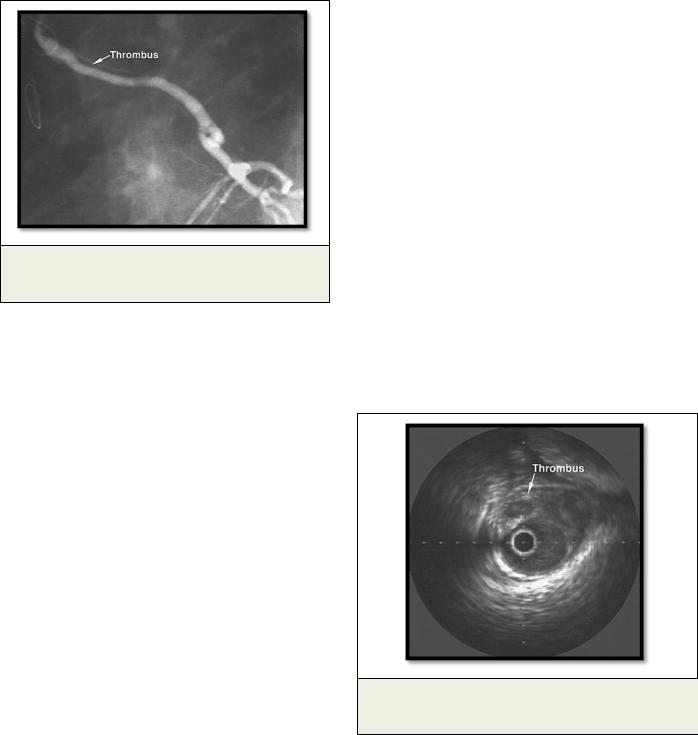

Рис. 1. КАГ.

Протяженный тромбоз венозного шунта.

Рис. 2. Внутрисосудистый ультразвук.

Тромб в просвете венозного шунта.

тов в первый месяц после операции является тромбоз (Рис. 1, 2), возникающий вследствие совокупности таких компонентов, как изменения в стенке сосуда, реологический состав крови и скорость кровотока, что хорошо описано в триаде Вирхова (теория возникновения тромбофлебита):